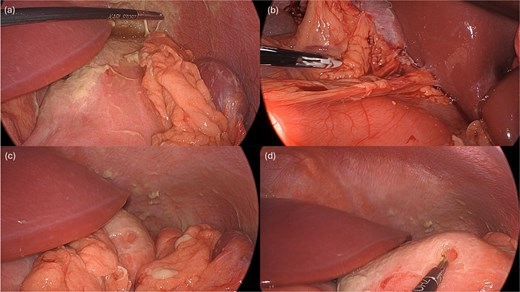

Laparoscopy began with placement of a 5 mm umbilical trocar and two additional 5 mm trocars in the right and left abdomen. Turbid fluid was encountered and suctioned. In the upper-abdomen, significant inflammatory omental adhesions were found against the right upper quadrant and gallbladder. A complex fluid collection with inflammation was identified in the left upper quadrant (Fig. 2). These inflammatory adhesions were carefully dissected using a Cool-SealTM device to visualize the pylorus and duodenum; however, inflammation around the gallbladder prevented full release of these adhesions. Mobilization of the gastrocolic ligament revealed a normal posterior gastric wall. Because inflammatory exudates obscured the anterior stomach and the first and second part of the duodenum, making the perforation’s origin (duodenal or gastric) initially unclear, simultaneous intraoperative-endoscopy was requested for precise localization.

Intraoperative pictures demonstrating the sequelae of the hollow viscus perforation. The pictures in (a) and (b) demonstrate contamination and associated inflammatory adhesions in the left and right upper quadrant, respectively. The pictures in (c) and (d) demonstrate the antral perforation. The tip of the Maryland dissector was able to insert into the perforation (d) to assist with identification of the perforation endoscopically for closure.

The gastroenterology team performed concurrent endoscopy using. With air insufflation and transillumination, a small pinpoint perforation was clearly identified on the anterior surface of the gastric-antrum (Figs 2 and 3).

To aid endoscopic visualization of the small perforation, a Maryland grasper was gently inserted into it (Fig. 2); the grasper’s tip, visualized endoscopically, confirmed the exact location. The remainder of the esophagus, stomach, and duodenum appeared normal. The Overstitch™ endoscopic-suturing device, mounted on a double-channel therapeutic endoscope and utilizing a tissue-helix for full-thickness bites, was used. Three full-thickness inverted figure-of-eight 2–0 Prolene sutures were placed at the perforation. Laparoscopic visualization confirmed full-thickness suture placement before the sutures were cinched, effectively closing the gastric wall defect (Fig. 3).